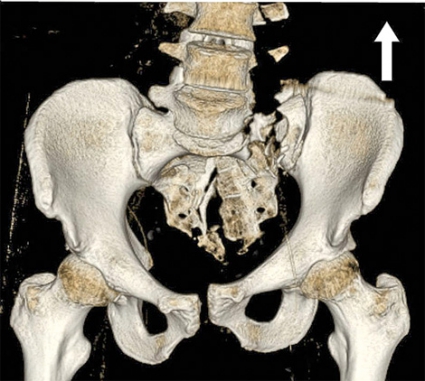

• Vertikalt våld, vilket ger vertikal fraktur i sakrum, i sakroiliakaled eller ilium och med vertikal dislokation. Skadan uppkommer vanligen vid fall från höjd (Figur 4, underst).